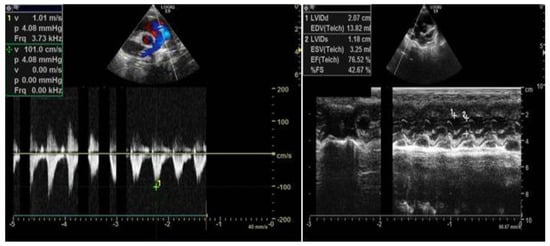

2. Case Report

2.1. Clinical Data